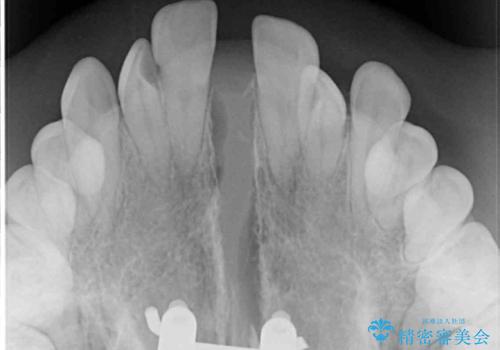

上顎骨を拡大したことで、下顎の歯列を上顎が受け入れられるようになりましたが、インビザラインでは咬み合わせを改善させることができなかったため、ワイヤー矯正にて仕上げることとしました。

ワイヤーを使用したものの、上下前歯のオープンバイトがなかなか改善されませんでしたが、患者希望により治療終了となりました。